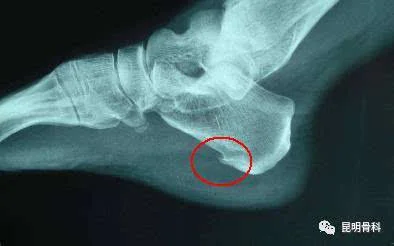

跟骨骨刺

不是. 骨刺,学名叫骨赘,它是人体代偿性增加局部骨骼强度的结果.

脚后跟骨刺图片

足跟骨刺若是在生活中,常常感觉到脚后跟疼痛,并且往往刚沾地,就会有